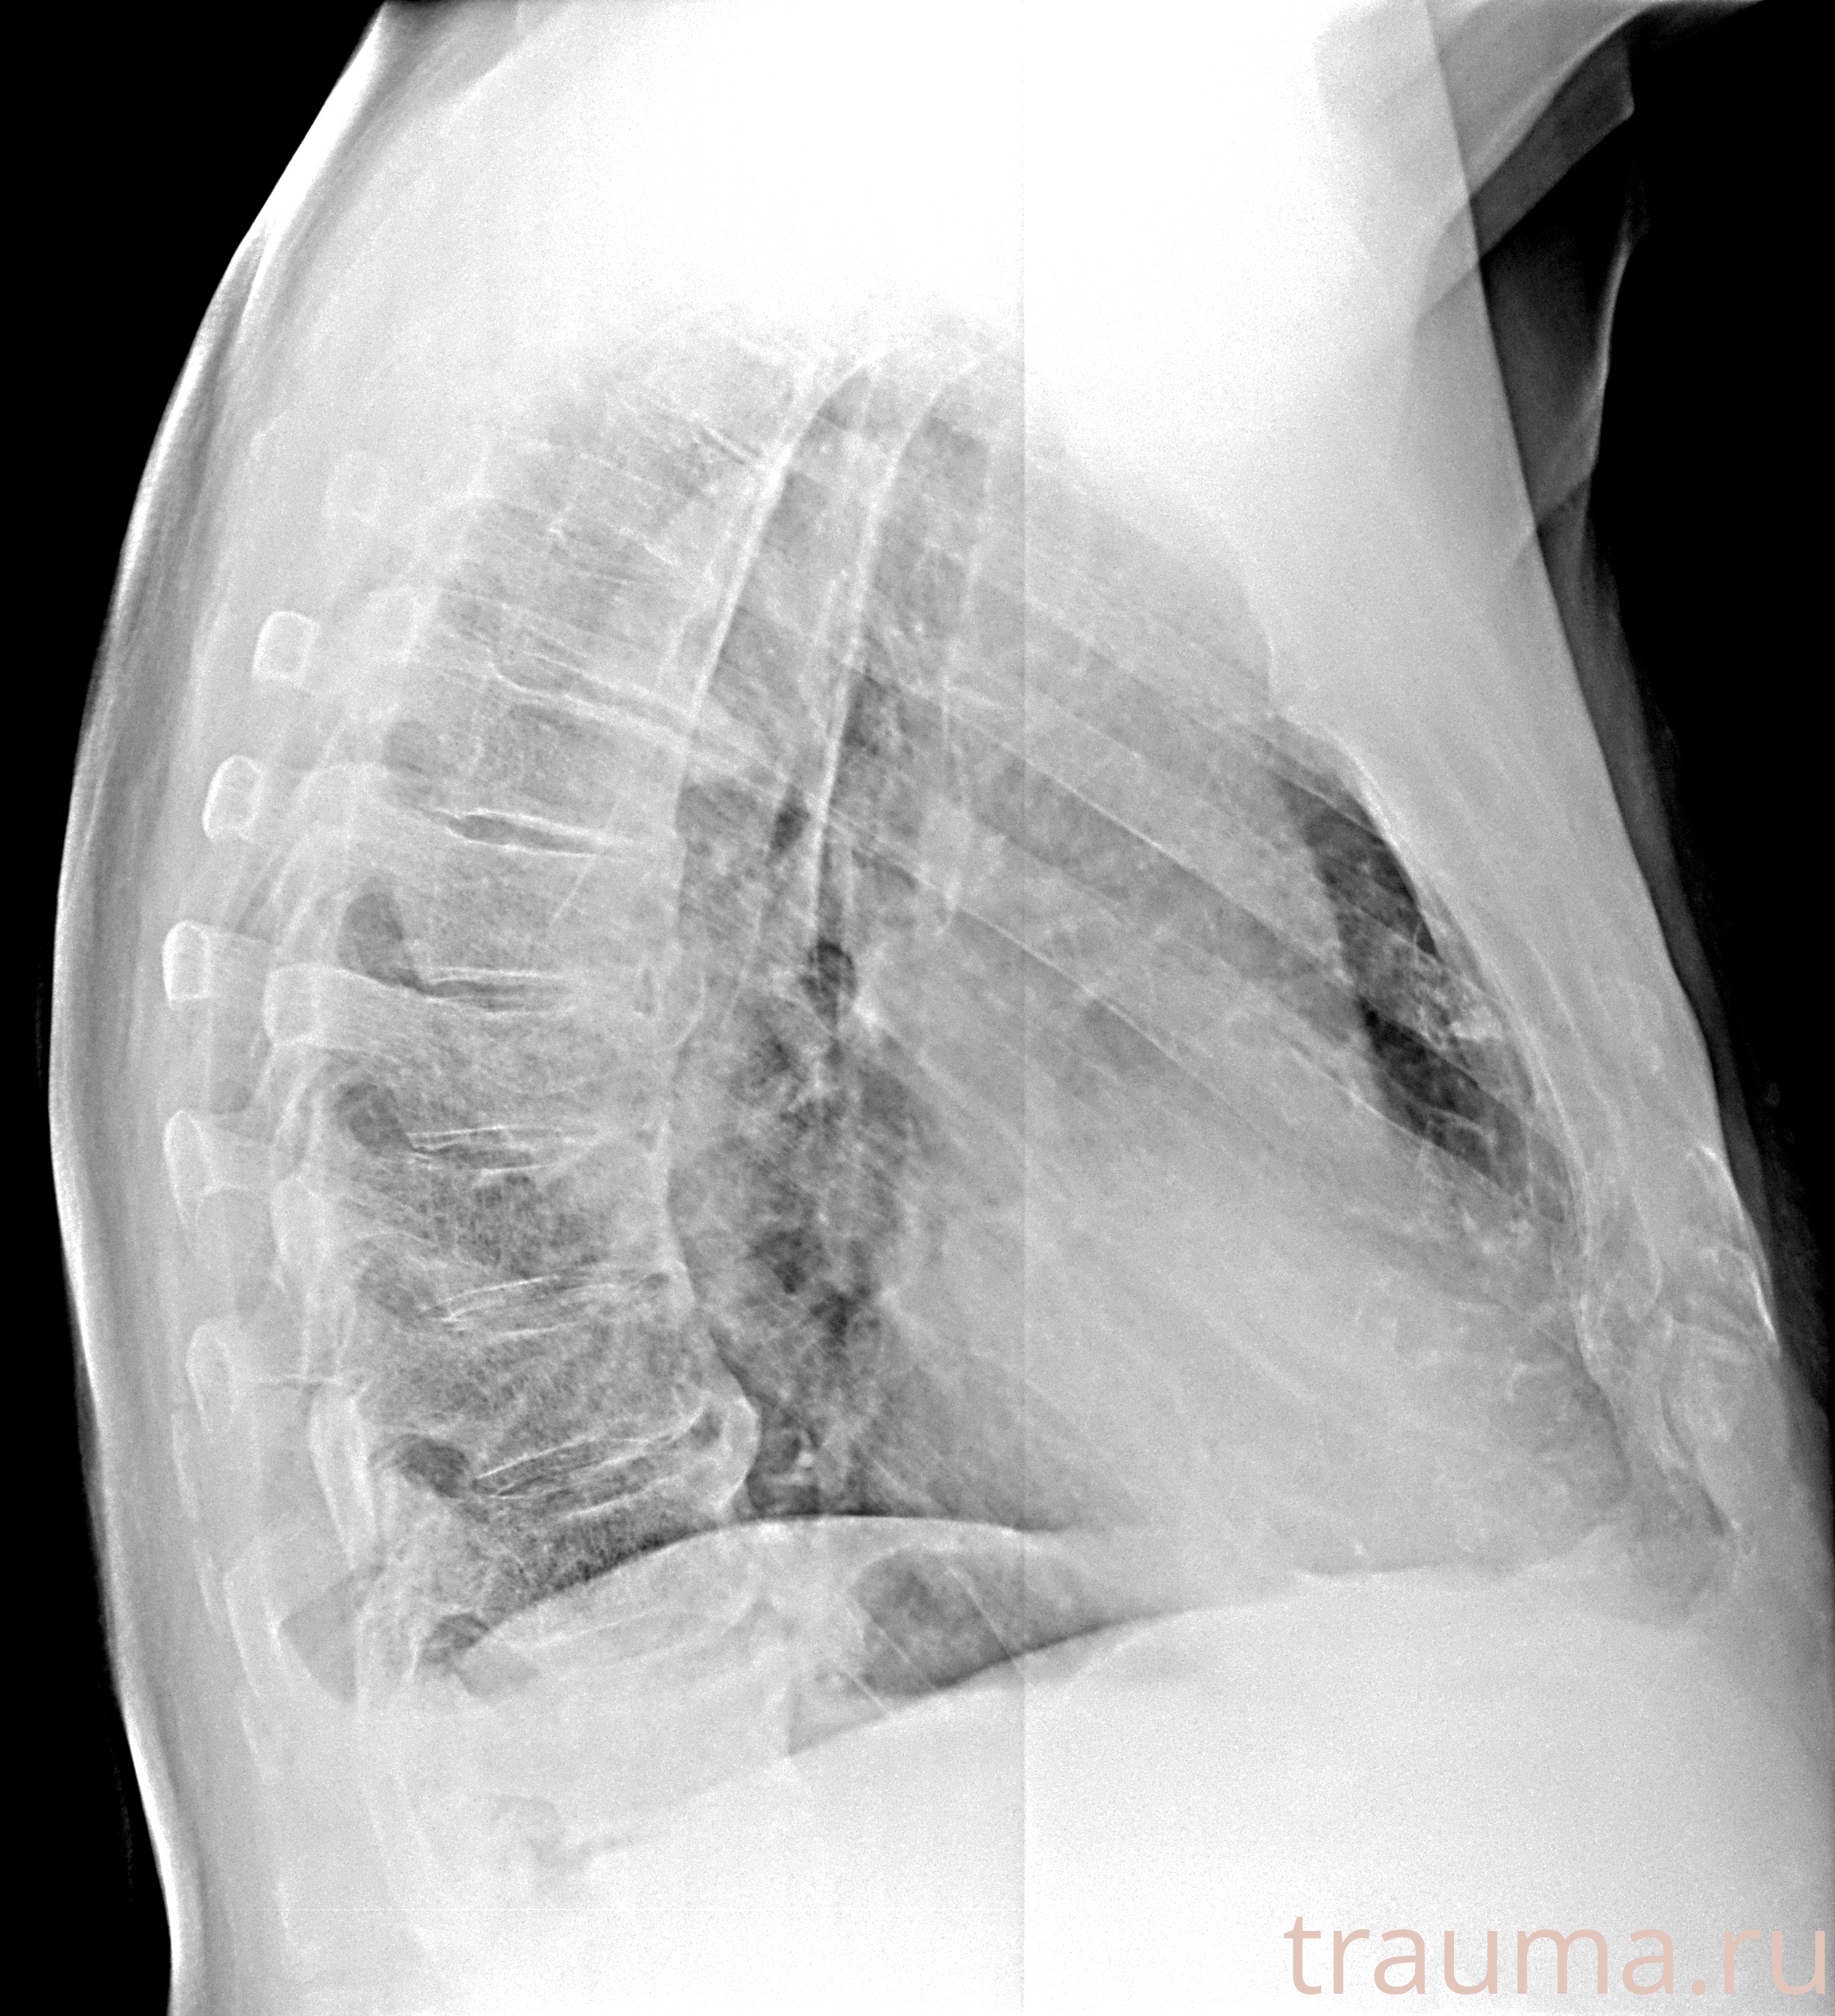

Рентгенограммы

Рентген на дому: по вашему адресу приезжает врач-рентгенолог, травматолог-ортопед с мобильным рентгеновским аппаратом, проводит диагностику травмы или заболевания, делает необходимые рентгенограммы, дает рекомендации по дальнейшему лечению. Получить качественные снимки в домашних условиях возможно благодаря уникальной методике, разработанной МосРентген Центром для института  Склифосовского

при переломе шейки бедра и пневмонии от компании МосРентген Центр - партнера Института имени Склифосовского